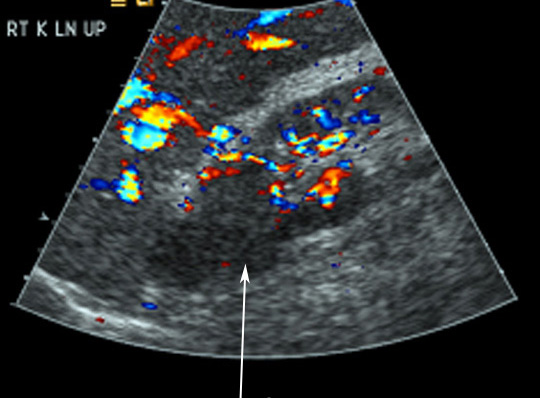

US

- Isoechoic mass or hypoechoic mass

- Hyperechoic mass

Renal Cell Carcinoma

- Almost isoechoic mass from upper pole

- No posterior wall enhancement to suggest a cyst